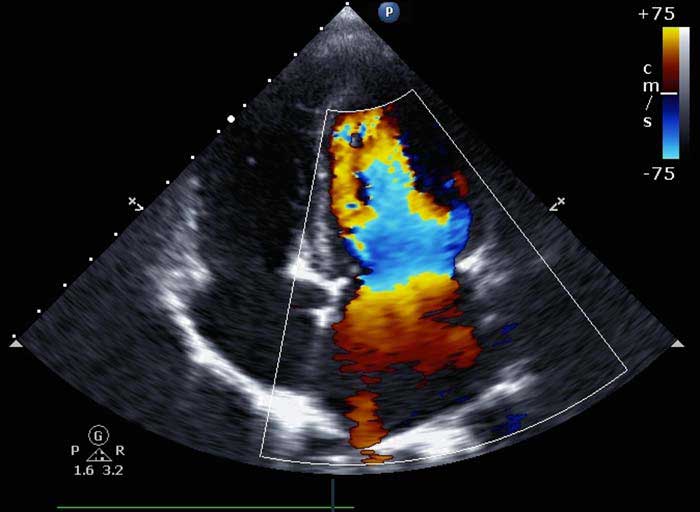

1. سونوگرافی کالر داپلر (Color Doppler)

نمایش جریان خون با رنگهای مختلف

رنگ قرمز و آبی جهت حرکت خون را نشان میدهد

کاربرد گسترده در بررسی عروق، واریس و بارداری

| کالر داپلر (Color Doppler) | نمایش رنگی جریان خون، جهت و سرعت | نمایش جهت و سرعت | تشخیص انسداد، واریس، بررسی جریان خون جنین |

تفاوت کالر داپلر با داپلر معمولی چیست؟

کالر داپلر جریان خون را بهصورت رنگی نمایش میدهد و درک آن سادهتر است.

تفاوت کالر داپلر با داپلر معمولی چیست؟

کالر داپلر جریان خون را بهصورت رنگی نمایش میدهد و درک آن سادهتر است.